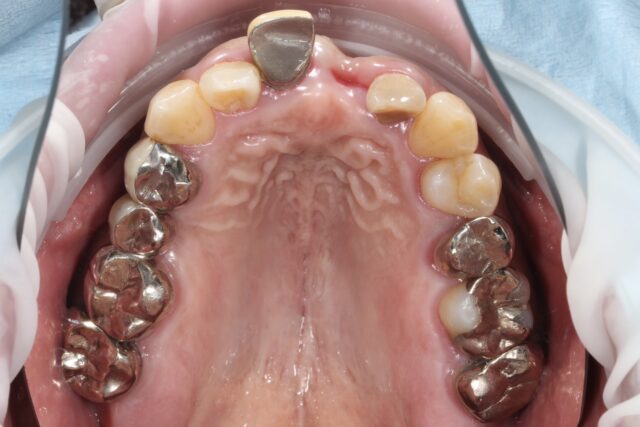

before

after